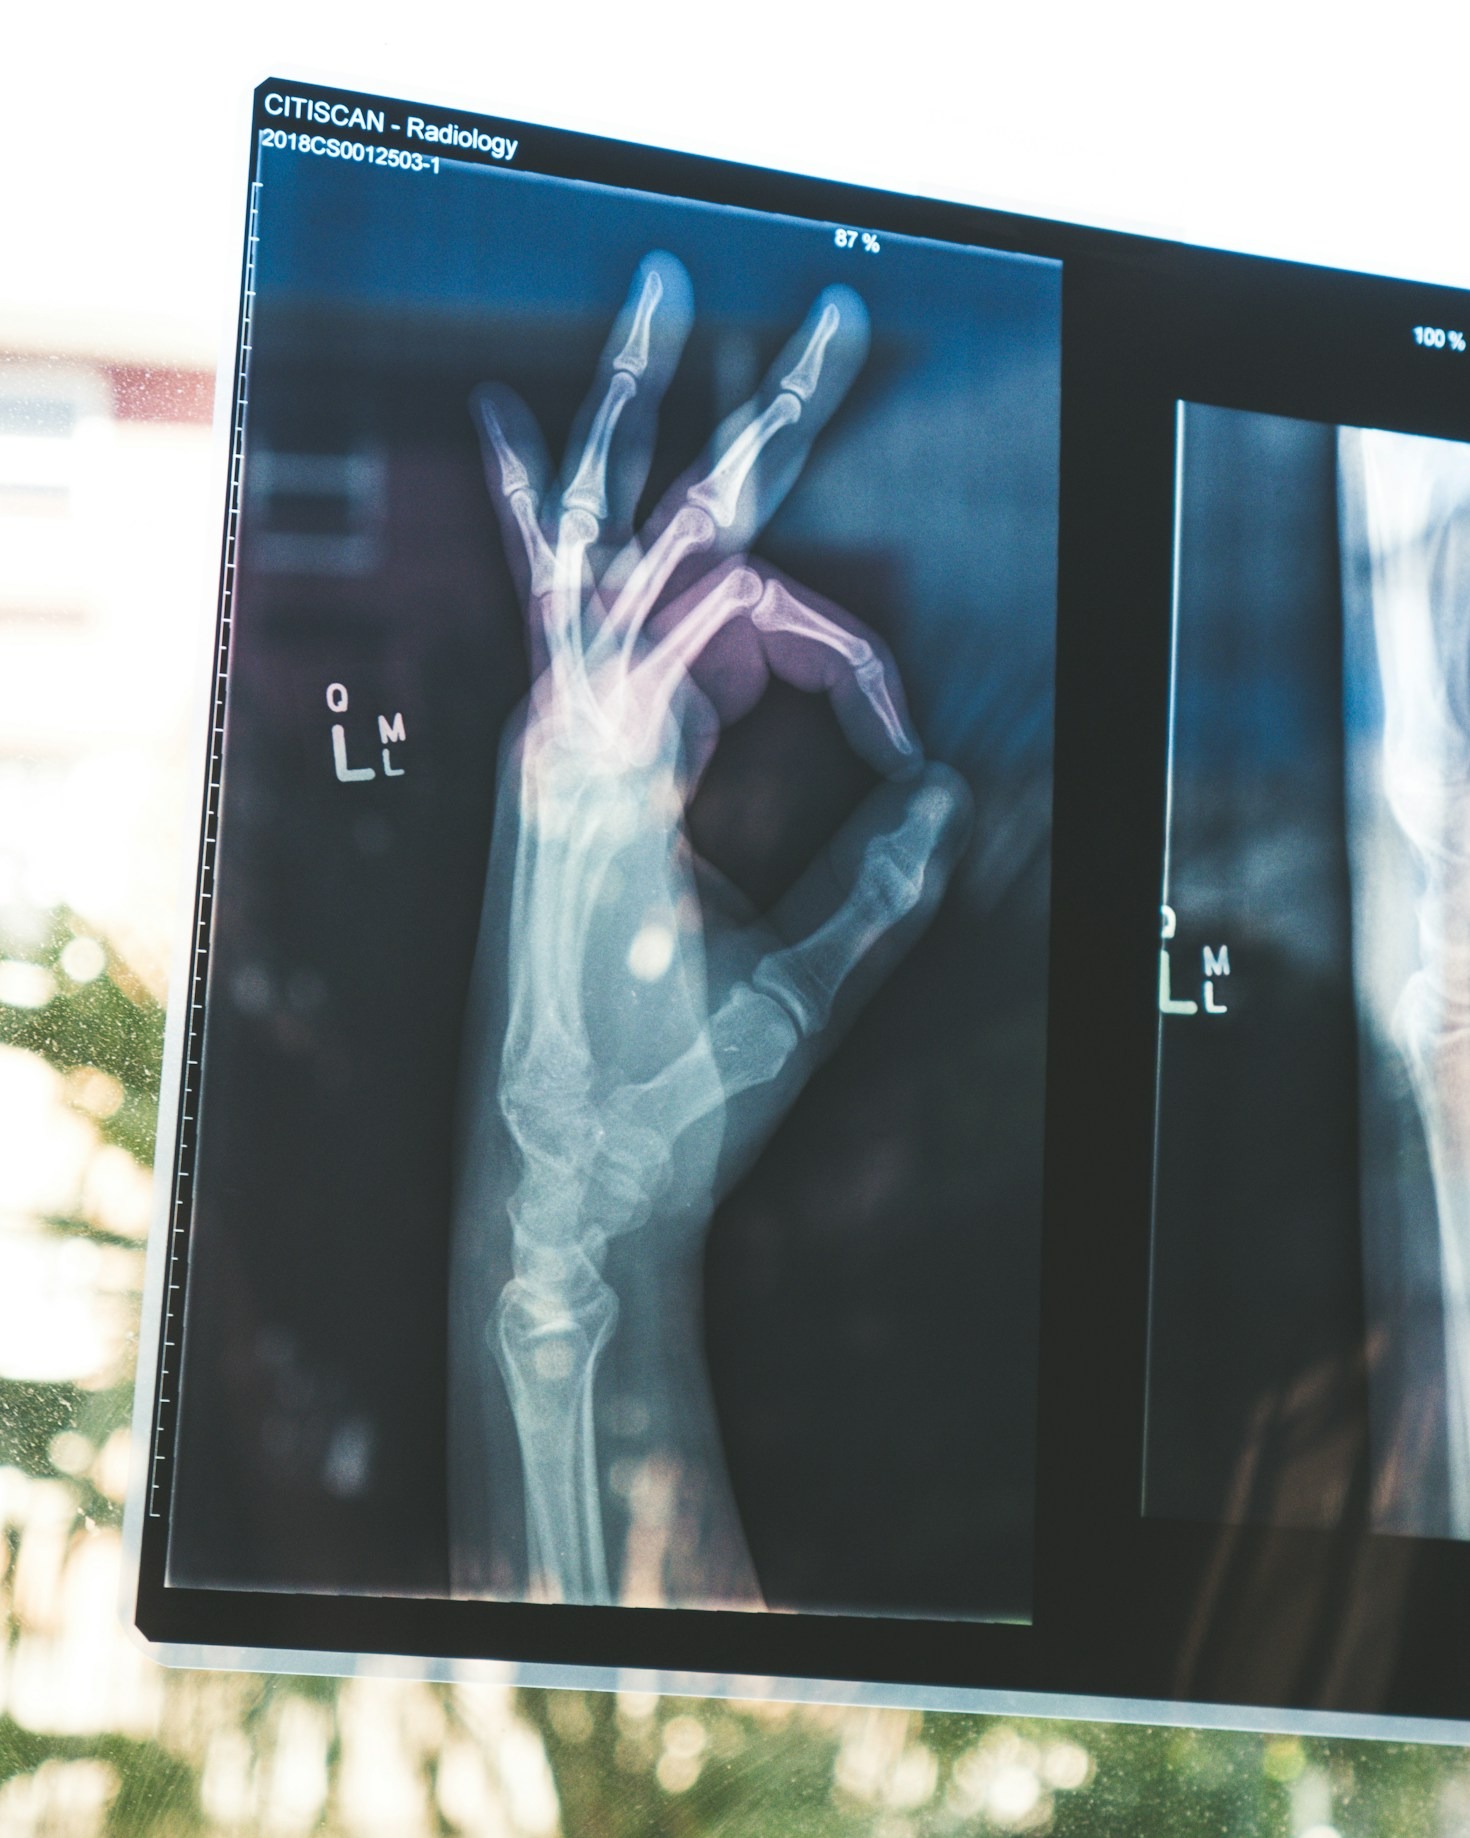

A área da radiologia está em constante evolução. Novas técnicas, novos equipamentos e o impacto da automação em todos os setores alicerçados pelo uso da inteligência artificial obriga os profissionais dessa área a estarem preparados para os desafios que se apresentam. Educação contínua é a palavra de ordem. Todo conhecimento atualizado é o que vai…